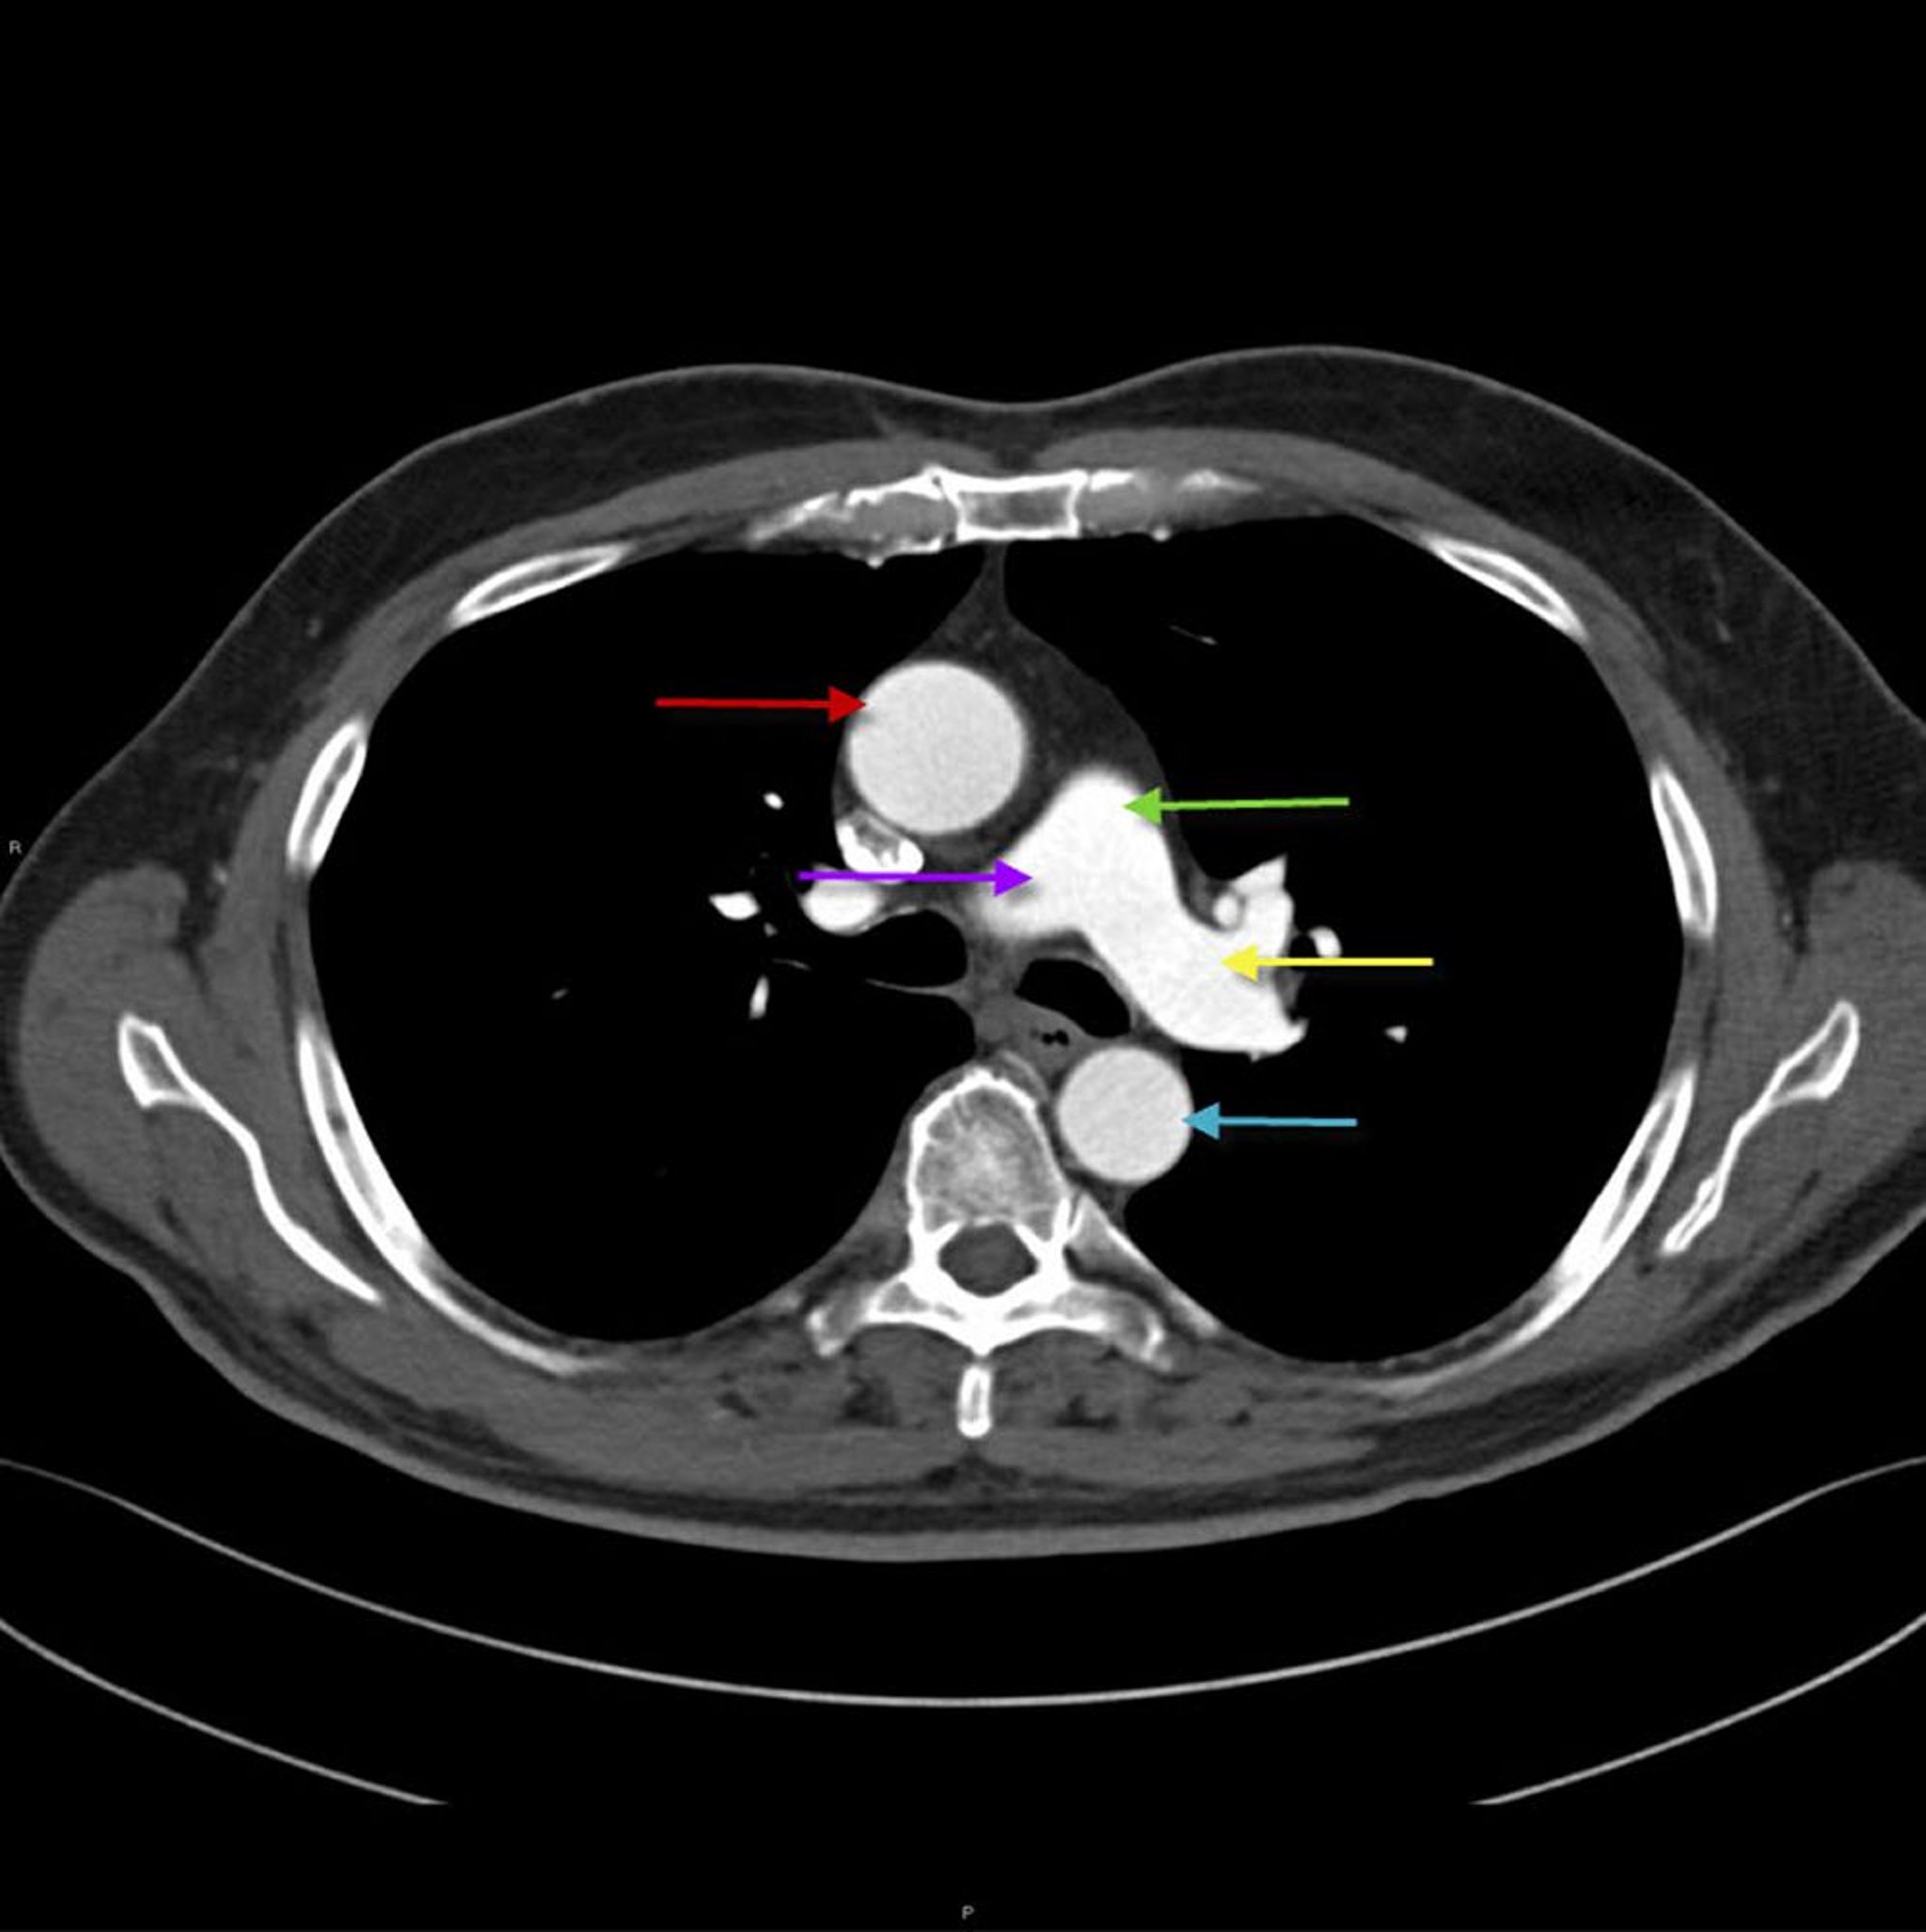

TDM du thorax montrant l'anatomie de l'aorte et de l'artère pulmonaire

Cette image montre l'aorte thoracique ascendante (flèche rouge) avec l'aorte thoracique descendante (flèche bleue). L'artère pulmonaire principale (flèche verte) se divise en artère pulmonaire droite (flèche violette) et gauche (flèche jaune).